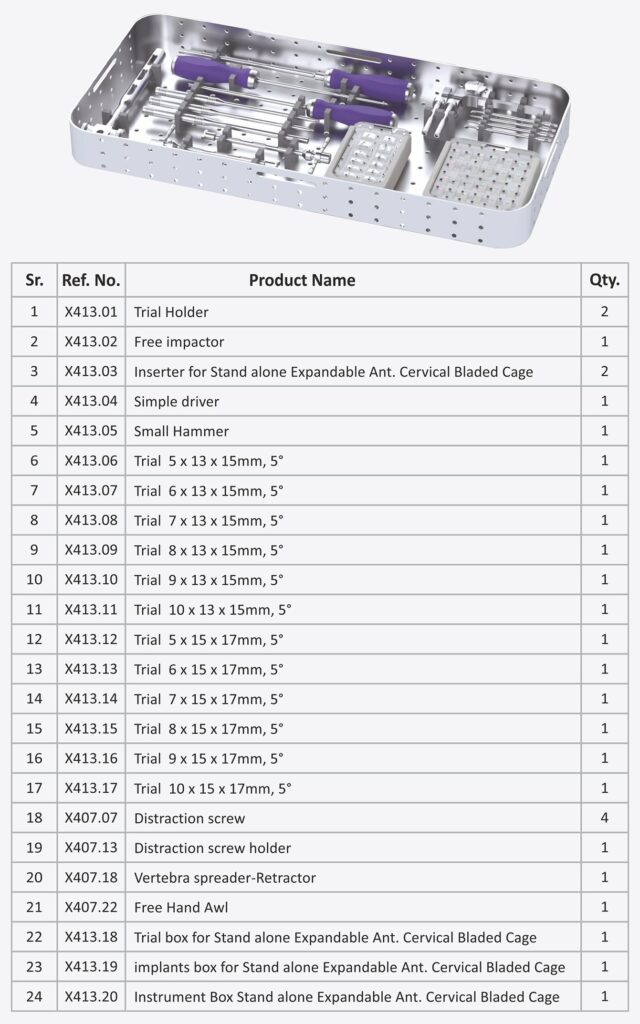

The Stand-Alone Expandable Anterior Cervical Bladed Cage is a next-generation spinal implant designed for Anterior Cervical Discectomy and Fusion (ACDF) procedures. Engineered for superior anatomical fit, this cage combines expandable height technology, integrated anchoring blades, and zero-profile fixation in a single, self-contained device—offering unmatched ease of use, stability, and clinical outcomes.

Size 13 x 15 mm and Lordosis 50

Height: 5mm to 10mm (1mm Variation)

Size 15 x 17 mm and Lordosis 50

Height: 5mm to 10mm (1mm Variation)